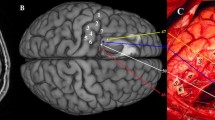

A 62-year-old woman, right-handed, was admitted in our department after acute onset episodes of visual troubles in the right hemifield. She was working as an administrative manager in a petrochemical company. MRI revealed a contrast-enhanced left superior parietal lobule lesion (see Fig. 1). Surgery in the awake condition was offered, in order to resect a marginal zone around the contrast-enhanced area while minimizing functional risk. Tumor resection was complete, and the patient was discharged at post-operative day 3. Pathological analysis confirmed the diagnosis of glioblastoma.

Intraoperative photography. Upper left, cortical mapping. Tag 2, right arm tingling at 2.5 mA. Lower left, electrodes location. Upper right, final mapping. Tag 6, when stimulating at 3 mA, the patient said “I do not feel my (right) hand where I see it”. Lower right, neuronavigation snapshot locating tag 6 in the preoperative MRI

Two electrode strips of 6 × 1 contacts each (Dixi medical, Chaudefontaine, France, radius 2.5 mm, inter-electrode distance 1 cm) were placed over the postcentral gyrus (contacts 1 to 6, from dorso-mesial to ventro-lateral) and the angular gyrus/lateral occipital cortex (contacts 7 to 12, from anterior to posterior), respectively (see Fig. 1).

Cortical mapping revealed a site (tag 2) whose stimulation at an intensity of 2.5 mA generated tingling in the right arm. At the end of the resection, several functionally eloquent sites were identified in the white matter: dorso-mesially (tag 3, not visible on the intraoperative photography) a site generating feeling of vibration in the right leg when stimulated at an intensity of 3 mA; these fibers were detected also more ventrally (tag 4). Just latero-dorsally to the latter, another white matter site generated a discrepancy between visually and proprioceptively perception of the right hand (the patient spontaneously reported during stimulation “I do not feel my hand where I see it”) when stimulated at an intensity of 3 mA (see Fig. 1, tag 6). Finally, the stimulation of tag 5 at 5 mA induced a vertigo.

Strip 1 (referential montage: reference minus contact) was positioned all over the most rostral portion of the superior parietal lobule and post-central gyrus (see Figs. 1 and 2). Strip 2 (differential montage between adjacent contacts) was located over the angular and lateral occipital cortex (see Fig. 1). When stimulating tag 6, the larger ACEP was recorded on contact 1 of strip 1 (see Fig. 3 and Tables 1 and 2). A smaller ACEP was recorded on contact 2, with the very same shape of contact 1. Finally, an even smaller ACEP was recorded on contact 6. No ACEPs were recorded by contacts 3, 4, and 5 in strip 1 or by any contacts in strip 2.

A 1 cm-diameter spherical ROI corresponding to tag 6 was manually positioned on the postoperative T1 anatomical image (see Fig. 2), based on the neuronavigation snapshot and intraoperative photography (see Fig. 1). This ROI defined a seed for dissecting the postoperative tractogram. The electrode contacts were also positioned on the postoperative T1 anatomical image, following the methodology described in [2].